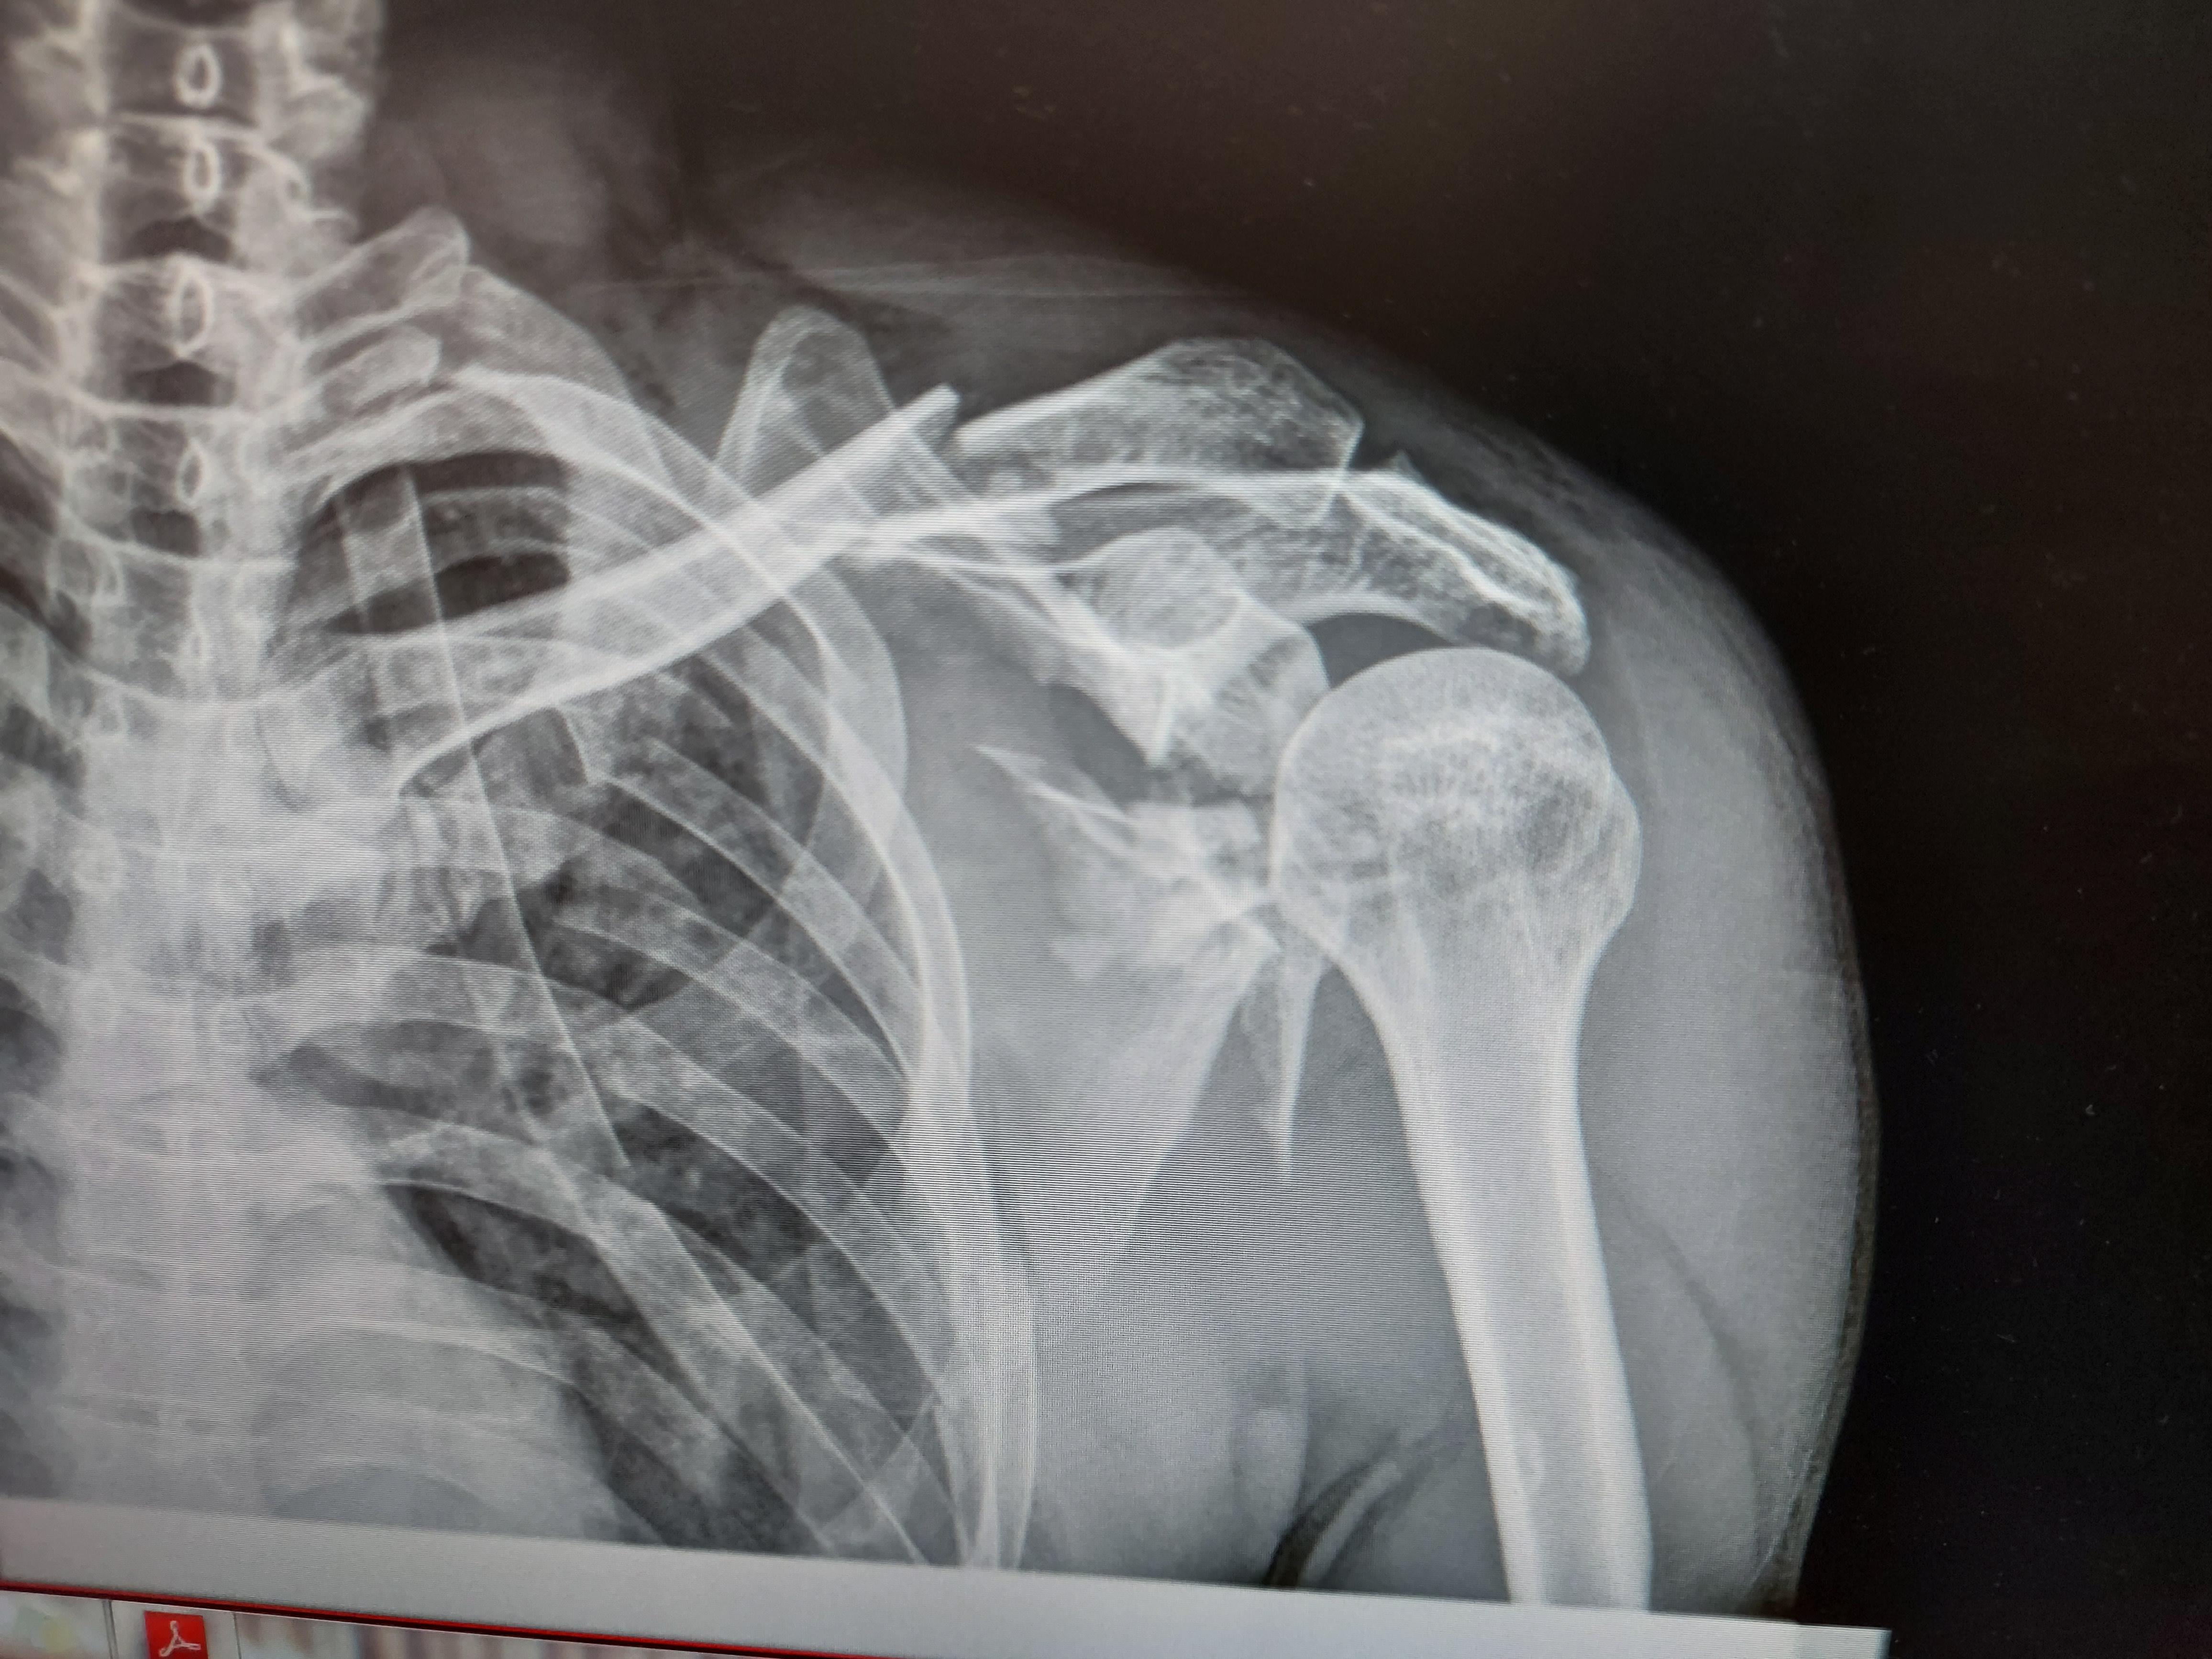

Scapula Fracture X Ray at Rhonda Fisher blog Scapula Fracture Case Law The plaintiff sustained a fractured right clavicle, a fracture of the blade of. In mlalandle v road accident fund 2011 (6j2) qod 90 (ecp): In mark alan roe v raf case no 16157/2009 sghc an award of r650 000,00 for general damages where the plaintiff had. He sued the defendant, the. Authority on humerus elbow fractures: [1] on 7 april. Scapula Fracture Case Law.

Scapula Fracture X Ray Scapula Fracture Case Law In mark alan roe v raf case no 16157/2009 sghc an award of r650 000,00 for general damages where the plaintiff had. In mlalandle v road accident fund 2011 (6j2) qod 90 (ecp): Authority on humerus elbow fractures: Here plaintiff sustained fractures of the thoracic vertebrae causing paraplegia; Although the vast majority of scapula fractures may be safely managed with.. Scapula Fracture Case Law.